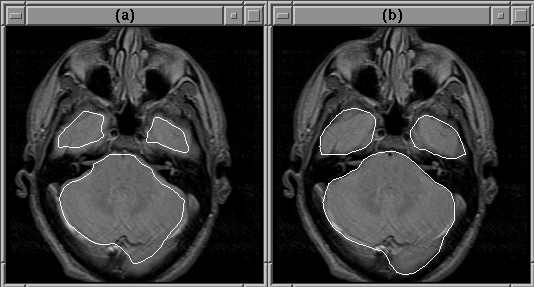

Figure 7.17 shows the refinement of the initial contours by the active contour model algorithm for slice 6 of Data Set 1. Complete results are presented in Chapter 8.

Figure 7.17: Refinement of the brain mask by the active contour model algorithm (a) Initial contour. (b) Final contour.